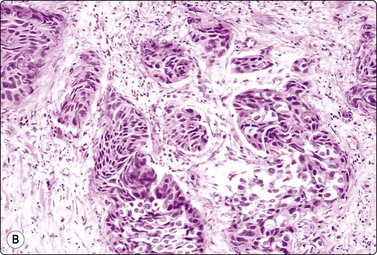

Adenocarcinoma of prostate (Figs 13.5-13.8)4,5,27,34,36,37,39

image image image

Fig. 13.5 Well-differentiated adenocarcinoma

Cohesive sheets of atypical glandular epithelium; mild nuclear enlargement and anisokaryosis; crowding of nuclei; absence of cytoplasmic granules. Note microacinar pattern in B and prominent nucleoli and a mitotic figure in C (A and B, DQ; C, Pap, HP).

Criteria for diagnosis

Cell-rich smears (if derived from a solid carcinoma nodule),

Decreased cell cohesion, variable numbers of single cells,

Three-dimensional clusters, microacini,

Interconnected large mono- or bilayered sheets with honeycomb pattern (well-differentiated carcinoma),

Indistinct cell membranes; high N : C ratio,

Nuclear and nucleolar enlargement; variable pleomorphism,

Intracytoplasmic granules only rarely present,

Positive staining for PSA and/or PSAP, absence of cytokeratin-positive basal cells.

In smears of prostatic carcinoma, sheets of benign glandular epithelial cells are commonly seen side-by-side with aggregates of malignant cells (Fig. 13.6), reflecting the diffusely infiltrative growth of the tumor. Benign and malignant cells can be directly compared (very helpful clue) and differences in cytoarchitectural features are easily appreciated. Nuclear enlargement is one of the most important criteria of malignancy. Nucleolar enlargement is better demonstrated in Pap-stained smears.

Absence of visible cell membranes, nuclear crowding and overlapping and dissociation of cells are other important criteria. The presence of coarse intracytoplasmic secretory granules makes malignancy unlikely, but they can occasionally be found in cells from well-differentiated adenocarcinoma. Cytoplasmic vacuolation may be seen in both benign and malignant cells. Nuclear pleomorphism and chromatin abnormalities are obvious in less well-differentiated cancers but may be subtle in well-differentiated carcinomas, rendering a definitive malignant diagnosis difficult (Fig. 13.5). Demonstration of basal epithelial cells by immunocytochemistry may be of help in the distinction between well-differentiated adenocarcinoma and adenosis or basal cell hyperplasia,5 but interpretation is more difficult than in histologic sections. Immunostaining is a useful tool for the diagnosis of prostate cancer at metastatic sites.42 Results may be conflicting in metastases of poorly differentiated carcinomas.

If only a small number of atypical cells are found in a predominantly benign cell population, great caution should be observed in making a definitive diagnosis of malignancy. Sources of atypical cells have been referred to elsewhere.4,5,8,9 In case of doubt, the patient should be submitted to systematic TNCB taken according to a standardized protocol.

Regarding cytological grading of prostatic adenocarcinoma, see below and Figures 13.5 to 13.8.

Well-differentiated carcinoma (Fig. 13.5)

Malignant microacini: abundant ill-defined cytoplasm occupying the central zone encircled by a crown of nuclei. Microacini vary noticeably in size and shape. The high frequency of microacini is one of the most important diagnostic criteria,36

Mono- and bilayered large interconnected strands of epithelium,

Few single cells,

Mild anisonucleosis,

Mild hyperchromasia,

Mild or even absent nuclear atypia,

Inconspicuous nucleoli (Pap enhances nucleoli).